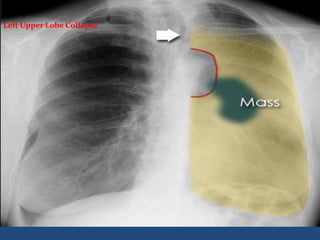

Left Upper Lobe Collapse

 Left lower lobe has increased in volume to compensate

volume loss and can be seen wrapping round the

medial side of the collapsed upper lobe. This is known

as the 'Luftsichel' (air crescent) sign .

Left Upper Lobe

Collapse